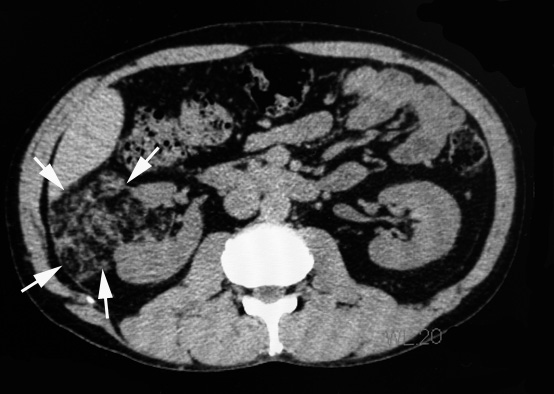

右腰痛のため受診。精査で右腎に出血をともなう直径7cmの腫瘤を認めた。angiomyolipomaの出血と診断し, 出血の消失をまって右腎摘出術をおこなう。